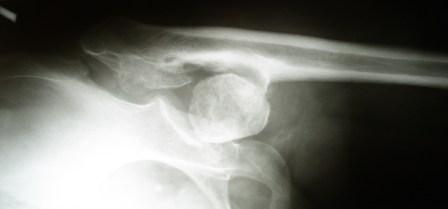

Хотелось бы услышать Ваше мнение по лечению больной 45 лет. Никаких

медицинских документов нет. Со слов больной лечили по поводу

врожденного вывиха бедра. В 1985г. остеотомия нижней трети бедра и

удлинение в аппарате Илизаровна 5см. В настоящее время укорочения

конечности нет. Обратилась по поводу выраженного болевого синдрома,

который усилился в течение последних двух лет. Судя по рентгенограммам

- имел место coxa vara coli lisis с патологическим вывихом бедра.

Любое низведение бедра даст грубое удлинение конечности. остеотомии в

условиях головки-секвестра мне кажутся бесперспективными.